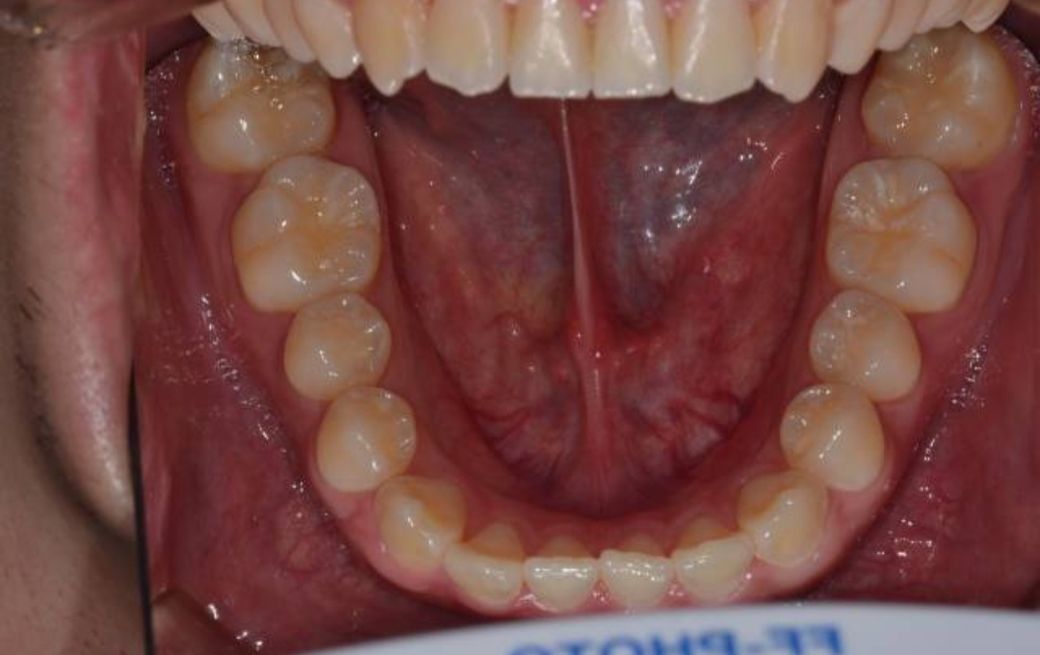

• 2번 째 사진